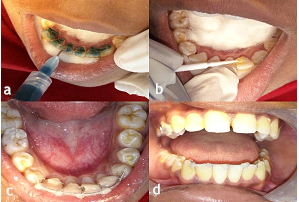

Oral prophylaxis followed by proper isolation was done intraorally. Following etching (Figure 6a) and application of a bonding agent (Figure 6b), the appliance was fixed in its desired position with light-cured composite resin (Figure 6c and 6d).

Figure 6.a) Etching the lingual surfaces of the lower anterior teeth; b) Application of a bonding agent on the etched teeth; c) Application of light-cured composite resin on the lower anterior teeth after fixing the appliance on the selected teeth; d) Intraoral frontal view of the appliance after being fixed on the selected teeth.